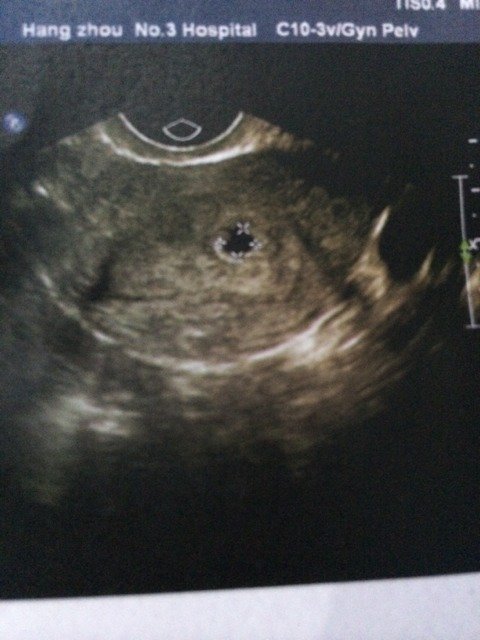

11.25号大姨妈 吃完药12.9号 又来了一次大姨妈 然后去医院检查怀孕了 请教下 6.7毫米 5.8毫米 大概推算是多少天